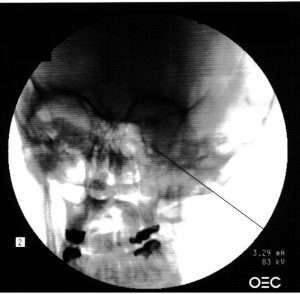

Injections of local anesthetics or other appropriate medications into areas where the sensory nerves are can help to manage many chronic pain conditions. In Chronic Pain the ongoing pain signal that travels from the site of pain to spinal cord and ends up in brain causes some changes in the central nervous system. These changes make the pain to become chronic and persistent with gradual changes in their qualities. Nerve blocks or blocking the transmission of pain signals by the nerves using local anesthetic injections can help to manage this condition. Blocking the nerve would temporarily stop the pain signals sent through these pathways and help to down grade the central nervous system changes. Their effects are still under investigation and although there are not enough controlled randomized clinical trials done in this area to demonstrate their effect, their use in practice has helped thousands of patients over years of their sufferings. It is important that these injections be performed by physicians well trained in intervetional pain management and in well equipped clinics. If side effects happens, it is important that the physician be well trained to deal with any side effects and the facility be well equipped by all emergency protocols and equipments to help the patient. In many cases having the procedure done by some sort of guidance, like ultrasound or fluoroscope can increase the effect and reduce side effects. Nerve block injections, like any other modalities in pain management should be used when indicated and be used as a part of multi-disciplinary pain management.